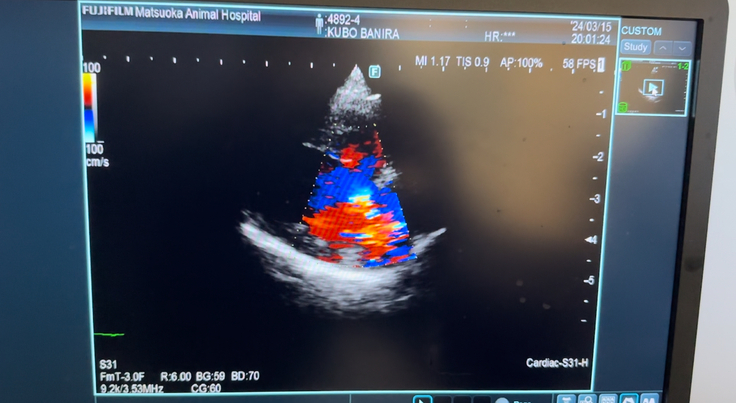

(心エコー画像。赤と青色以外が血液の逆流を示しています)

僧帽弁閉鎖不全症について

心臓の弁の問題になります。

心臓が収縮して血液を送り出すとき、僧房弁が完全に閉鎖せず、血液が逆流してしまう病気です。初期は無症状ですが進行すると肺水腫などの命に関わる状態(心不全)を発症することがあります。

犬の心臓病の中でも最も一般的になりやすく、心臓の内部にある弁に変性が起こることで通常は一方向に流れる血液が一部逆流してしまいます。

主に聴診、レントゲン検査、エコー検査により診断。